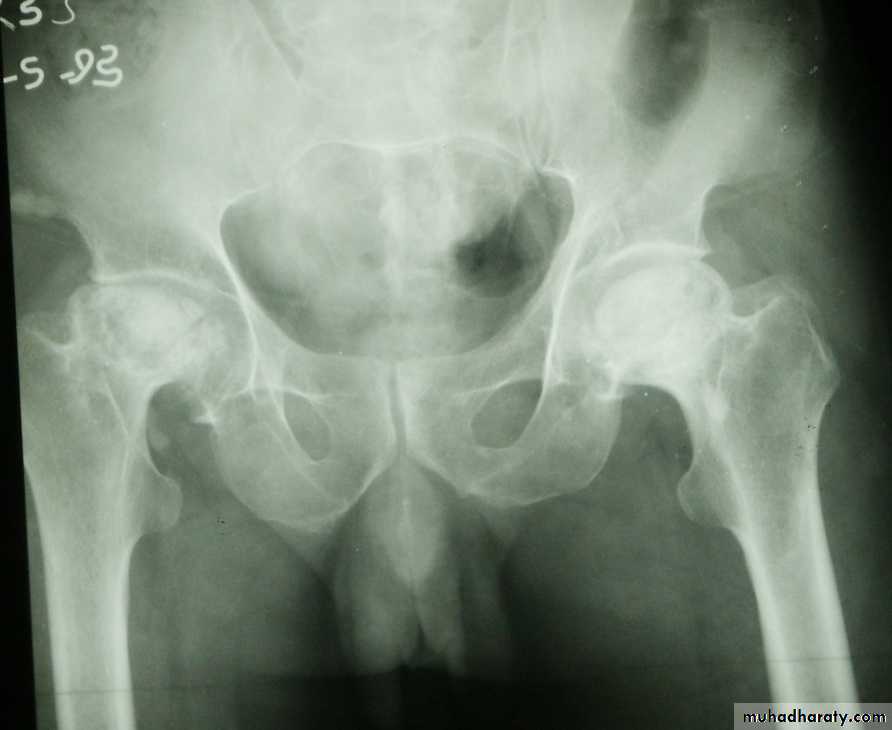

Posterior dislocation:

4 out of 5 traumatic hip dislocations are posterior.

Usually occur in road traffic accident when the knee striking the dashboard

the femoral head is forced out of its socket sometimes associated with fracture.

Clinically:

O\E

Leg is short, internally rotated, adducted ,

and slightly flexed hip.